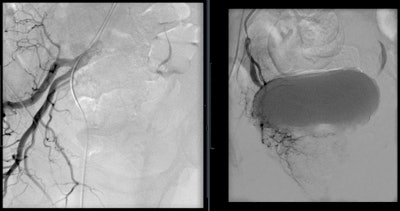

Prostate artery embolization is a noninvasive procedure that can bring long-term relief from symptoms caused by an enlarged prostate. This procedure works by closing the blood supply to the prostate, and, as a result, the prostate shrinks in size, reducing blockages and improving the symptoms.

PAE and hematuria

Prostatic hematuria is usually associated with BPH, iatrogenic urological trauma, or radiation therapy. Traditionally, it is treated conservatively with increased fluid intake, indwelling catheterization with bladder irrigation, and medical therapy. However, when these interventions fail, refractory hematuria is life-threatening. PAE has been shown to be an option for these patients. Although distinct prostatic hemorrhage is rarely seen on angiography, PAE is successful by obtaining complete arterial occlusion. By utilizing a superselective approach, control or cessation of hematuria within one to three days is achieved in 83% to 100% of patients.

Although the complications are minimal, PAE has adverse effects postprocedure. For patients without indwelling catheters, urethral burning during voiding and frequent urination have been the most common symptoms after PAE. However, these effects usually resolve within a week and can be treated with nonopioid analgesic medications. More serious complications are associated with nontarget embolization to the bladder, rectum, and penis. Ischemia to these organs is always possible and must be avoided through proper mapping via CBCT, microcatheterization for distal embolization, and calibrated microspheres for predictable embolization.